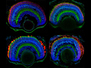

Sprouting Hairs

Most toddlers find endless fun in whirling around until they’re dizzy. But when dizziness strikes unexpectedly in old age it’s quite the opposite. One cause is the loss of hair cells in a part of the ear called the vestibular epithelium. Researchers investigated whether support cells in this epithelium could be coaxed into becoming hair cells by adding the gene ATOH1, as had been achieved in mice. Human vestibular epithelium was treated with a drug to destroy the hair cells. The support cells were then genetically manipulated to add ATOH1. Genetic analysis showed hundreds of hair cell genes were now switched on in these cells. Imaging them using electron microscopy revealed hair cell-like projections had sprouted from their tops (pictured). ATOH1 does seem able to kickstart the transformation of human support cells into hair cells. Research continues in the hopes of creating fully functional hair cells to treat balance disorders.